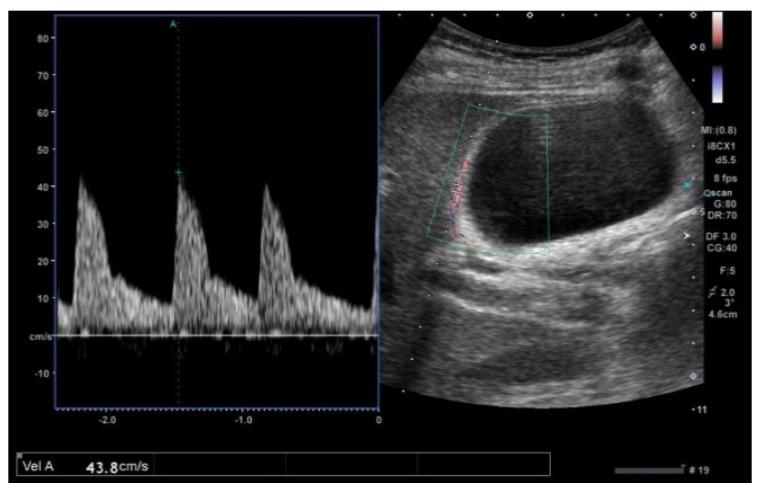

The most important role of ultrasound (US) in the management of gallbladder (GB) lesions is to detect lesions earlier and differentiate them from GB carcinoma (GBC). To avoid overlooking lesions, postural changes and high-frequency transducers with magnified images should be employed. GB lesions are divided into polypoid lesions (GPLs) and wall thickening (GWT). For GPLs, classification into pedunculated and sessile types should be done first. This classification is useful not only for the differential diagnosis but also for the depth diagnosis, as pedunculated carcinomas are confined to the mucosa. Both rapid GB wall blood flow (GWBF) and the irregularity of color signal patterns on Doppler imaging, and heterogeneous enhancement in the venous phase on contrast-enhanced ultrasound (CEUS) suggest GBC. Since GWT occurs in various conditions, subdividing into diffuse and focal forms is important. Unlike diffuse GWT, focal GWT is specific for GB and has a higher incidence of GBC. The discontinuity and irregularity of the innermost hyperechoic layer and irregular or disrupted GB wall layer structure suggest GBC. Rapid GWBF is also useful for the diagnosis of wall-thickened type GBC and pancreaticobiliary maljunction. Detailed B-mode evaluation using high-frequency transducers, combined with Doppler imaging and CEUS, enables a more accurate diagnosis.

超声(US)在胆囊(GB)病变管理中的最重要作用是更早地检测病变并将其与胆囊癌(GBC)区分开来。为避免漏诊病变,应采用体位改变以及具有放大图像的高频探头。GB病变分为息肉样病变(GPLs)和胆囊壁增厚(GWT)。对于GPLs,应首先分为有蒂型和无蒂型。这种分类不仅有助于鉴别诊断,也有助于深度诊断,因为有蒂癌局限于黏膜层。胆囊壁血流(GWBF)快速、多普勒成像时彩色信号模式不规则以及对比增强超声(CEUS)静脉期不均匀强化均提示GBC。由于GWT可在多种情况下出现,将其细分为弥漫性和局灶性形式很重要。与弥漫性GWT不同,局灶性GWT是GB特有的,且GBC发生率更高。最内层高回声层的连续性中断和不规则以及GB壁层结构不规则或破坏提示GBC。快速GWBF对壁增厚型GBC和胰胆管汇合异常的诊断也有帮助。使用高频探头进行详细的B超评估,结合多普勒成像和CEUS,可实现更准确的诊断。